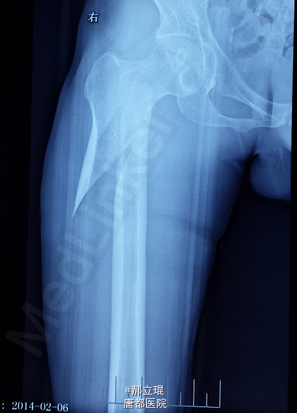

髓内钉

患者由于车祸,导致活动受限入院。

拍片,化验,X光片提示骨折。